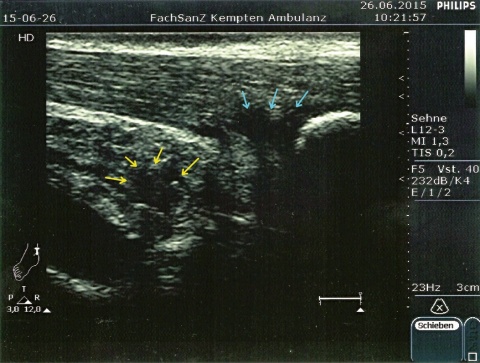

Ein einfacher Test zur Abgrenzung von einer Ruptur der Sehne mit Hämatom, Schwellung und eventuellem Tasten einer Delle ist nach wie vor der Simmonds-Thompson-Test (Plantarflexion des Fußes durch Kompression der Wadenmuskulatur bei intakter Achillessehne). Wie in der Kasuistik beschrieben, erfolgt die weitere Diagnostik mittels Sonographie der Ferse zur Darstellung einer Verdickung, Hypervaskularisation oder Zunahme von echoarmen Arealen. Zudem sollte eine Röntgenuntersuchung durchgeführt werden, um eine mögliche Haglund-Exostose zu detektieren. Eine Kernspintomographie der betroffenen Ferse eignet sich sehr gut zur Darstellung sowohl von strukturellen Veränderungen der Achillessehne, als auch begleitender Entzündungszeichen (siehe Abbildung 3).

Im Rahmen der Diagnostik in der truppenärztlichen Sprechstunde kann neben der obligaten klinischen Untersuchung eine sonographische Darstellung beider Achillessehnen im Seitenvergleich erste Anhalte für die Ursache der Beschwerdesymptomatik liefern.

Bildquellen: Abbildungen 1 und 2: P. Hoth, Kaufbeuren